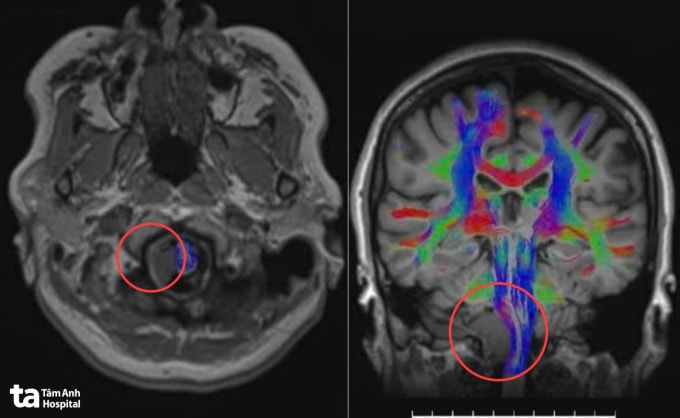

Ban đầu, bà Hạnh tê vùng lưỡi, đau đầu vùng chẩm đi khám phát hiện khối u não kích thước 2,5 cm ở vùng góc hành - tiểu não phải, chèn ép các dây thần kinh sọ thấp 9, 10, 11, 12. Đây là nhóm dây thần kinh điều khiển hoạt động nuốt, nói, cử động lưỡi, cơ cổ và động mạch cột sống.

Trước khi mổ, robot AI sử dụng công nghệ hòa hình đa lớp, tích hợp dữ liệu từ MRI và CT để tái tạo mô hình não 3D với độ phân giải cao. Nhờ đó, êkíp xác định rõ vị trí, kích thước cũng như mối liên quan giữa khối u và các dây thần kinh sọ 9, 10, 11, 12 cùng mạch máu nền sọ, lập kế hoạch tiếp cận tối ưu qua cửa sổ C1 - vùng nối giữa cổ và nền sọ.